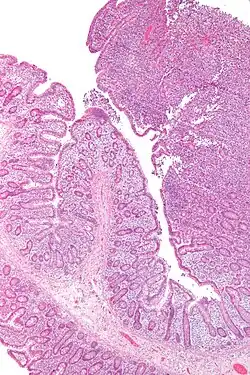

| Micrograph of an enteropathy-associated T cell lymphoma (upper right of image), a type of T cell lymphoma. H&E stain. | |